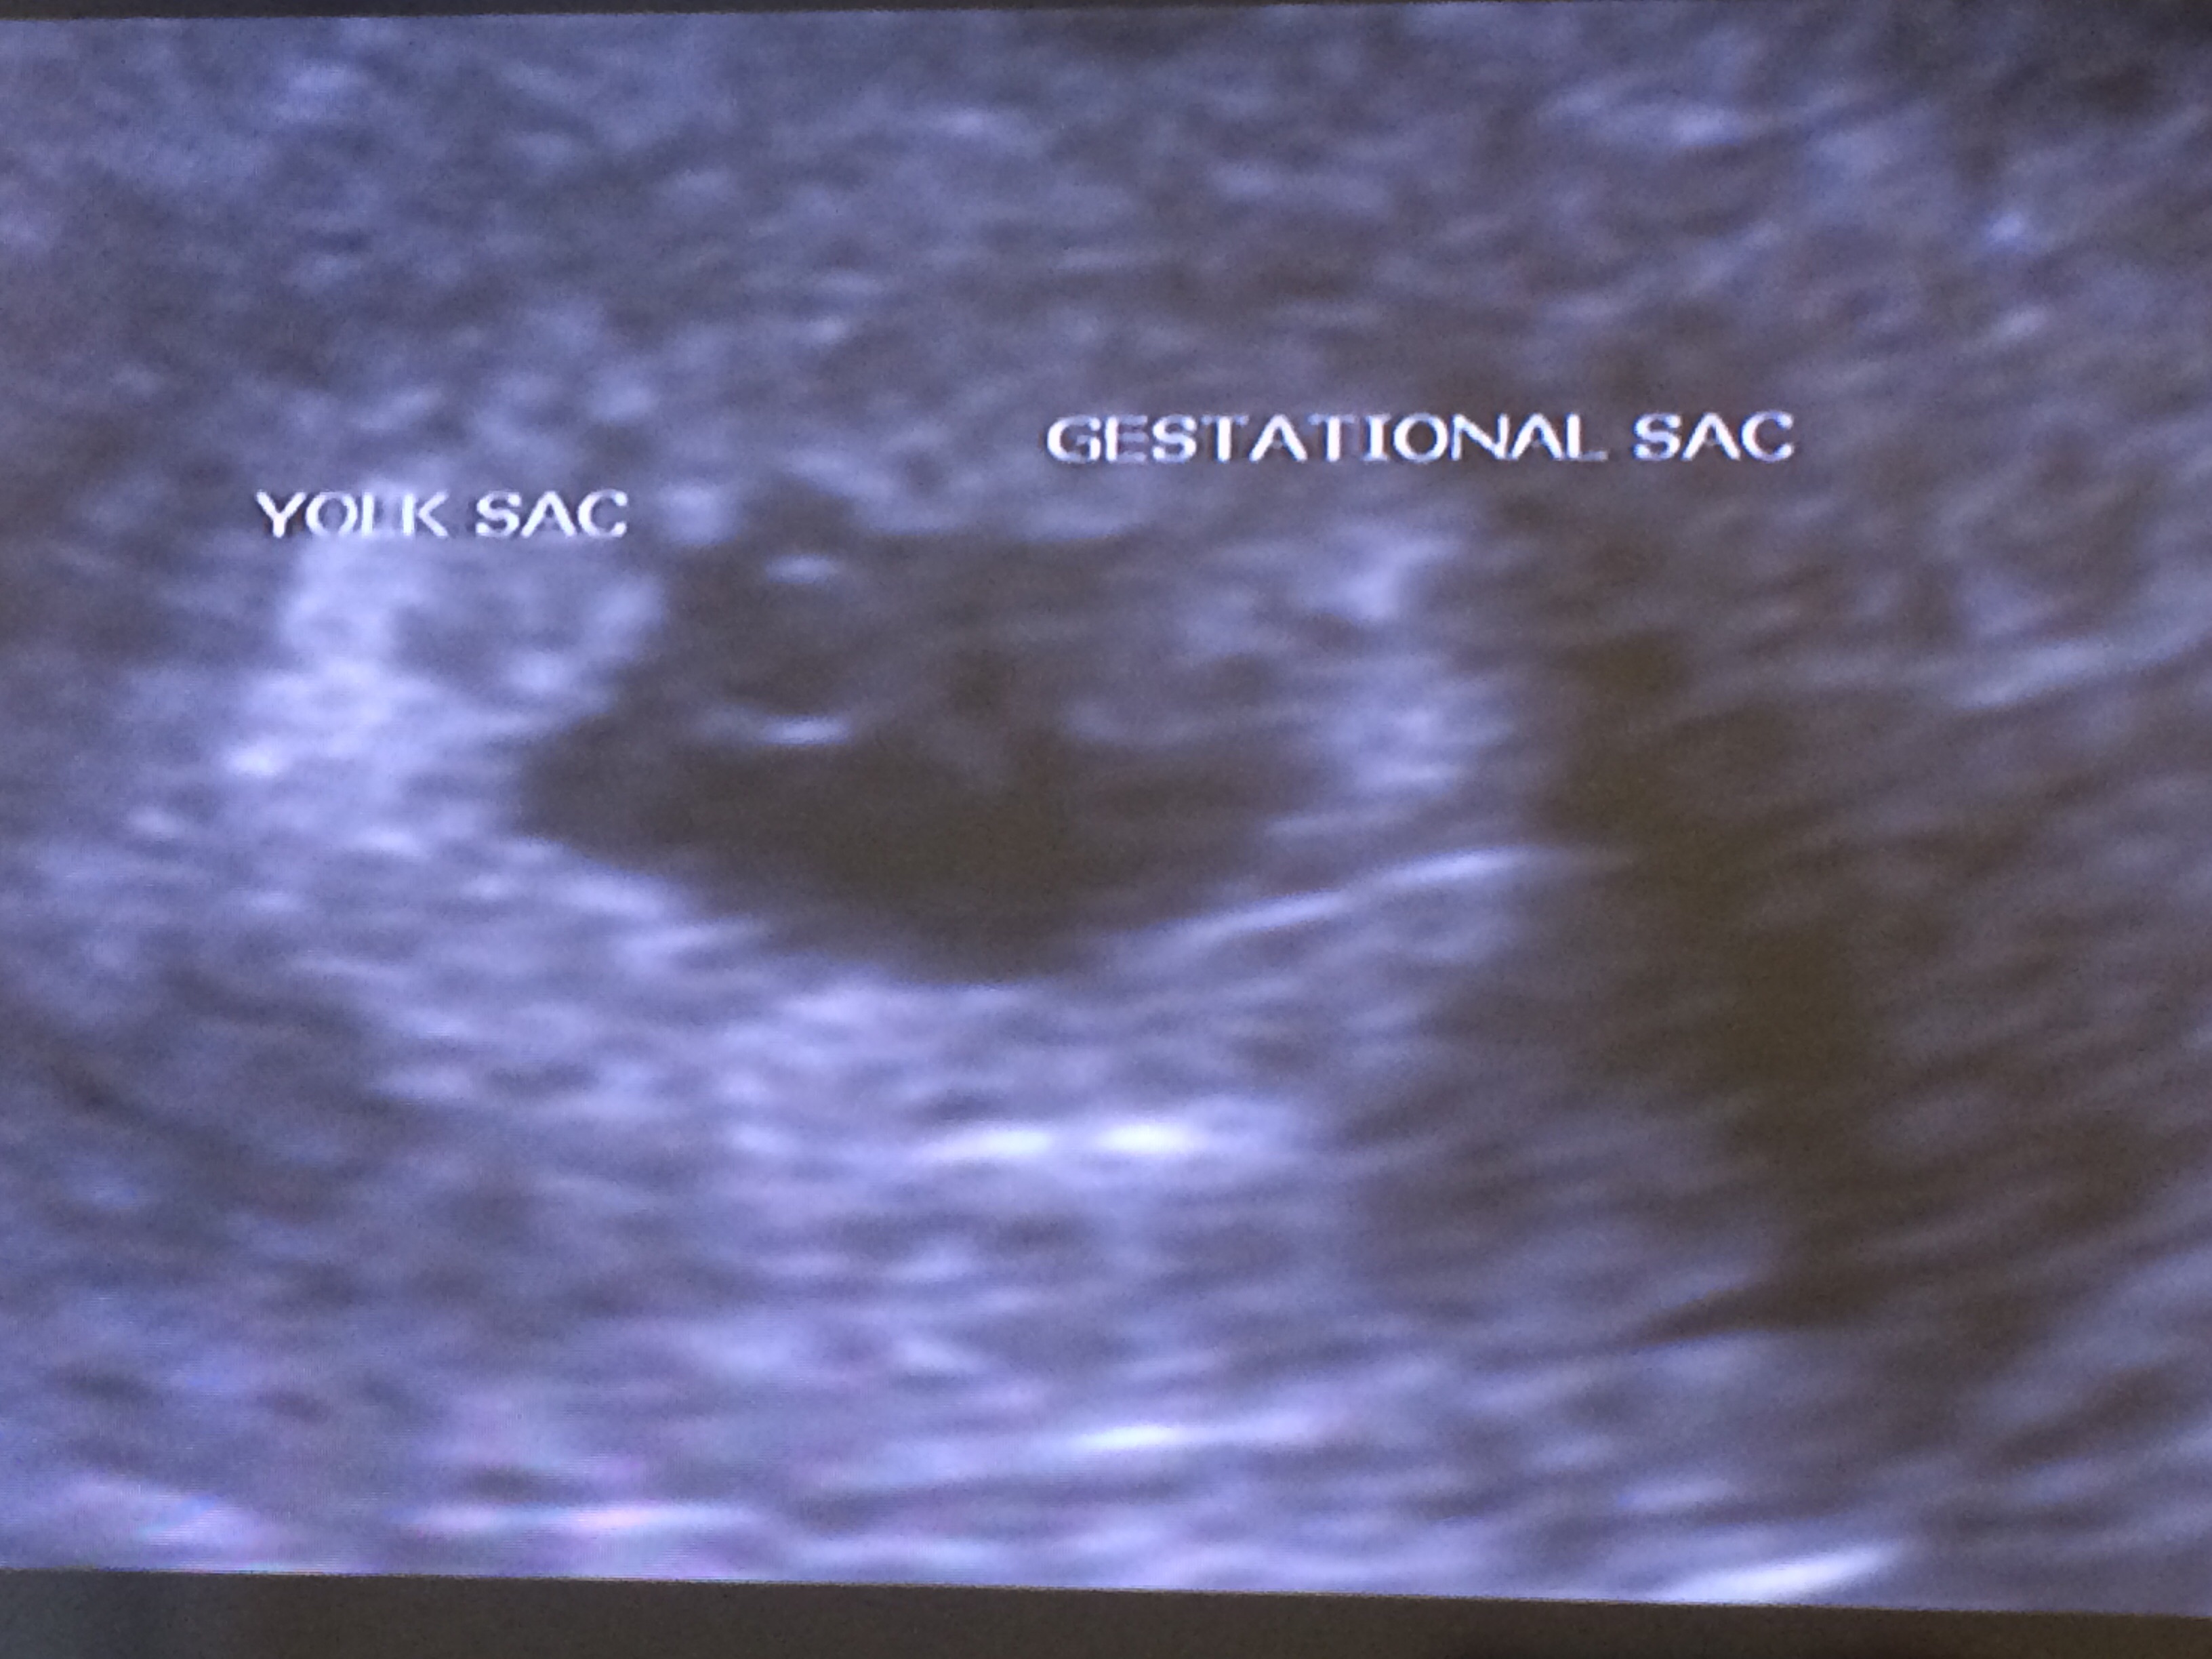

• Hello! I go to an RE so I had my first sono on Monday at 5 weeks, 3 days. We got to see the gestational sac & the yolk sac :) I go back next week for another sono, I hope to hear the heartbeat, but as long as everything is looking good I'm okay with that.

• Had my first one yesterday at 5 weeks and a couple days. Too early to see the heartbeat, just the gestational and yolk sac.